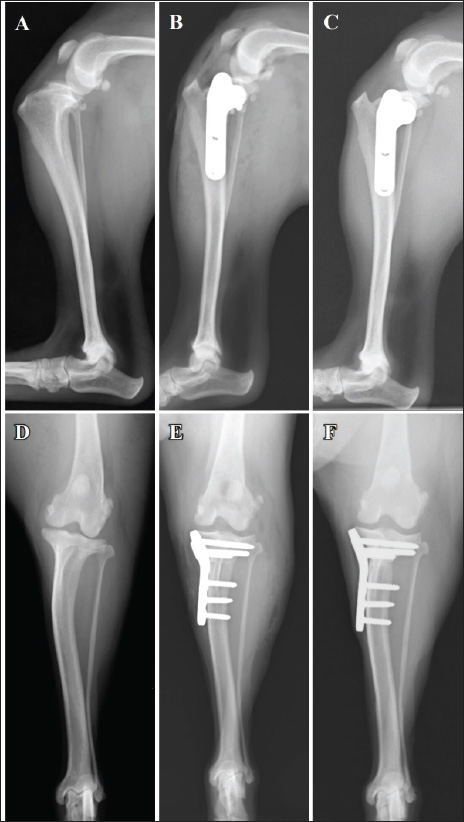

Left weight-bearing lameness with pain upon hyperextension and swelling in the left stifle joint were reported 8 weeks post-surgery of the right limb. The results of the cranial drawer and tibial compression tests performed as a part of the orthopedic examination of the left limb were positive. Radiography revealed the presence of the infrapatellar fat pad sign and cranial tibial luxation at the left stifle joint, with no obvious angular limb deformities (Fig. 4A and D). Ultrasonography of the left stifle joint revealed complete CCLR, moderate joint effusion, and medial buttress without damage to the caudal horn of the medial meniscus (Fig. 5A–C). Preoperative radiographs revealed a TPA of 25°. A 2.4-mm TPLO plate (VP4404-L3; DePuy Synthes Japan, Japan) was selected for TPLO. Identical to the measurements for the right limb, D1 and D2 for the left limb were 7.5 and 8.2 mm, respectively.

Postoperative radiography revealed that the TPA was 5° on both sides. The owner was satisfied with the postoperative weight-bearing ability of the limb while walking at the 4-week follow-up visit. A faint osteotomy line was visible, and radiography revealed aligned and positioned TPLO plates and bone segments with no displacement. No tibial translocation was detected during the compression test. The dog was able to use its right hind limb without any discomfort at the 8-week follow-up visit. The osteotomy line had disappeared, and radiography revealed aligned TPLO implants. Tibial translocation was not detected during the compression test. Minimal discomfort upon waking up was reported at the 14-week follow-up visit for the right limb (4-week follow-up for the left limb); lameness was not observed while walking or trotting. The tibial compression test results were negative for both limbs, and the rotated bone fragment showed complete fusion with the tibia of the right limb (Fig. 1C and F). A faint osteotomy line was observed in the tibia of the left limb. Radiography revealed no dislocation of the bone or the TPLO implants on the right or left sides. The owner was pleased with the significant improvement in walking ability. By the 13-week follow-up visit osteotomy line in the left limb was not visible, with no residual discomfort or lameness in either limb. The osteotomy line was not apparent owing to bone union (Fig. 4C). The implant alignment and bones remained stable (Fig. 4F).

Fig. 4. Mediolateral radiographs (A–C) and caudocranial radiographs (D–F) of the left limb. The infrapatellar fat pad sign and cranial tibial luxation at the left stifle joint before the surgery (A). No obvious angular limb deformity can be visualized (D). A postoperative radiograph acquired after the 2.4-mm TPLO plate placement (B and E). The tibial bone and bone fragment are completely fused at 13 weeks post-surgery (C). Additionally, the caudocranial radiograph at the 13-week (F). Follow-up visit shows no sign of dislocation of the implants.